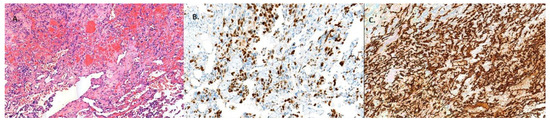

Introduction: Renal haemangioma is a benign tumour, and due to its characteristics, it must be distinguished from malignant diseases. We present a clinical case of primary renal angiosarcoma initially mistaken for haemangioma due to their similarity. Case report: A 58-year-old man was admitted to the hospital with suspicion of pulmonary embolism. The patient complained of pain on the left side. An ultrasound and CT scan of the abdomen showed a tumour mass ~20.5 × 17.2 × 15.4 cm in size in the projection of the left kidney. On CT images, there were data for clear cell renal clear cell carcinoma (ccRCC). A left nephrectomy was performed. However, histological examination revealed renal haemangioma. Three months later, the patient presented to the hospital with abdominal and lumbar pain. A CT scan showed multiple small hypoechoic foci up to 2 cm in size in the liver, lungs, and intra-abdominally, with the most data for carcinosis. Histological re-verification of the left kidney showed a renal vascular tumour with pronounced signs of infarction and necrosis with the majority of the evidence supporting angiosarcoma. Despite treatment, the patient’s outcome was fatal. Conclusions: Based on the clinical presentation, radiological images and histological examination data, the tumour was initially misdiagnosed as kidney haemangioma. Due to the rarity of this tumour, there are no established treatment protocols or clinical guidelines for managing primary kidney angiosarcoma. Full article

Show Figures

Figure 1